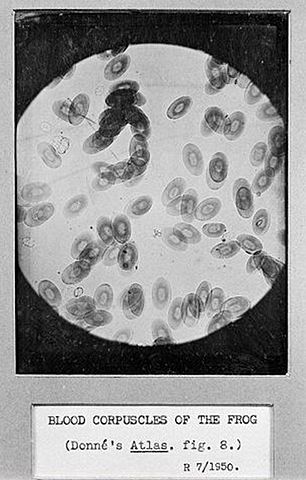

Se considera al francés Alfred Donne como el primer autor que reporto la presencia de plaquetas en la sangre, también se le atribuye al medico ingles George Gulliver

• Descripción de las plaquetas

Descripción de las plaquetas

En 1842, el ingles William Addison describe las plaquetas en su trabajo "Sobre los corpúsculos pálidos... en la sangre"